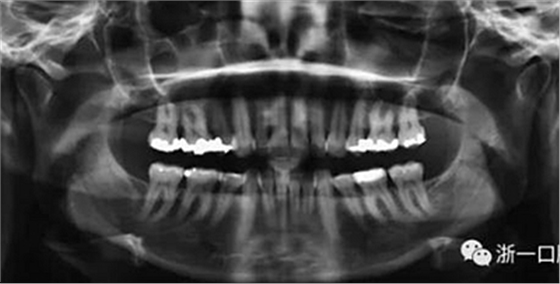

全麻下進(jìn)行上頜骨腭中縫骨皮質(zhì)劈開(kāi)及下頜正中劈開(kāi)術(shù)。手術(shù)后,用X光片檢查上頜骨和下頜骨中線(xiàn)切口的位置和方向。

術(shù)后第9天開(kāi)始旋轉(zhuǎn)擴(kuò)弓器,每天轉(zhuǎn)2次,每次轉(zhuǎn)90度,即擴(kuò)開(kāi)0.5mm。每隔1周進(jìn)行檢查,目標(biāo)上頜擴(kuò)開(kāi)9mm,下頜擴(kuò)開(kāi)6mm。18天后,上頜中切牙間出現(xiàn)8mm間隙。下頜出現(xiàn)6mm間隙,(于13天出現(xiàn)后,停止旋轉(zhuǎn)擴(kuò)弓器)。在擴(kuò)弓器旋轉(zhuǎn)3天后,拍片發(fā)現(xiàn)左下頜中切牙遠(yuǎn)中牙根中段有一條低密度陰影,臨床冷熱診反應(yīng)遲鈍,可能為術(shù)中損傷所致。牙體牙髓科會(huì)診,建議行根管治療,故行根管治療。

擴(kuò)弓保持8周后,除擴(kuò)弓器影響牙外粘接托槽,使用0.014鎳鈦絲進(jìn)行排齊、整平。旋轉(zhuǎn)停止后3個(gè)月拆除擴(kuò)弓器,全口粘接托槽,使用0.016niti繼續(xù)排齊整平。佩戴可摘保持器,保持上頜寬度。在使用至0.018x0.018niti7周,徹底排齊整平后,使用大弓型的0.016x0.022不銹鋼絲,繼續(xù)維持原有寬度,同時(shí)停止使用可摘保持器。掛II類(lèi)牽,糾正磨牙關(guān)系,使用鏈圈關(guān)閉散在間隙,少量使用IPR去除局部前牙的黑三角。術(shù)后9個(gè)月拍全景示,牙根平行度可,再無(wú)其他牙根出現(xiàn)問(wèn)題。1年7個(gè)月后治療結(jié)束。上下頜3-3舌側(cè)保持器+哈雷氏保持器進(jìn)行保持。